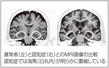

30分前に、見たり、聞いたり、体験した「近時記憶」が、海馬が萎縮して、脳に刻み込まれなくなります=図=。そのため、最近の旅行や孫の結婚式など、印象的な出来事でさえ忘れることがあるのです。これは、人や物の名前が出てこないような、加齢による「もの忘れ」とは少し違います。